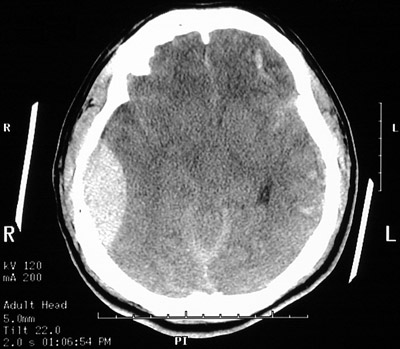

| In this axial head CT scan without contrast there is a large epidural hematoma on the right, with a "lens shaped" outline as the smooth dura is indented against the underlying cortex. The acute blood collection appears bright on CT. This patient fell from a height and struck the right side of his head, severing the middle meningeal artery. This epidural hematoma collected within hours. In the view seen below, at a level higher than the view above, there is a midline shift of the falx cerebri. |